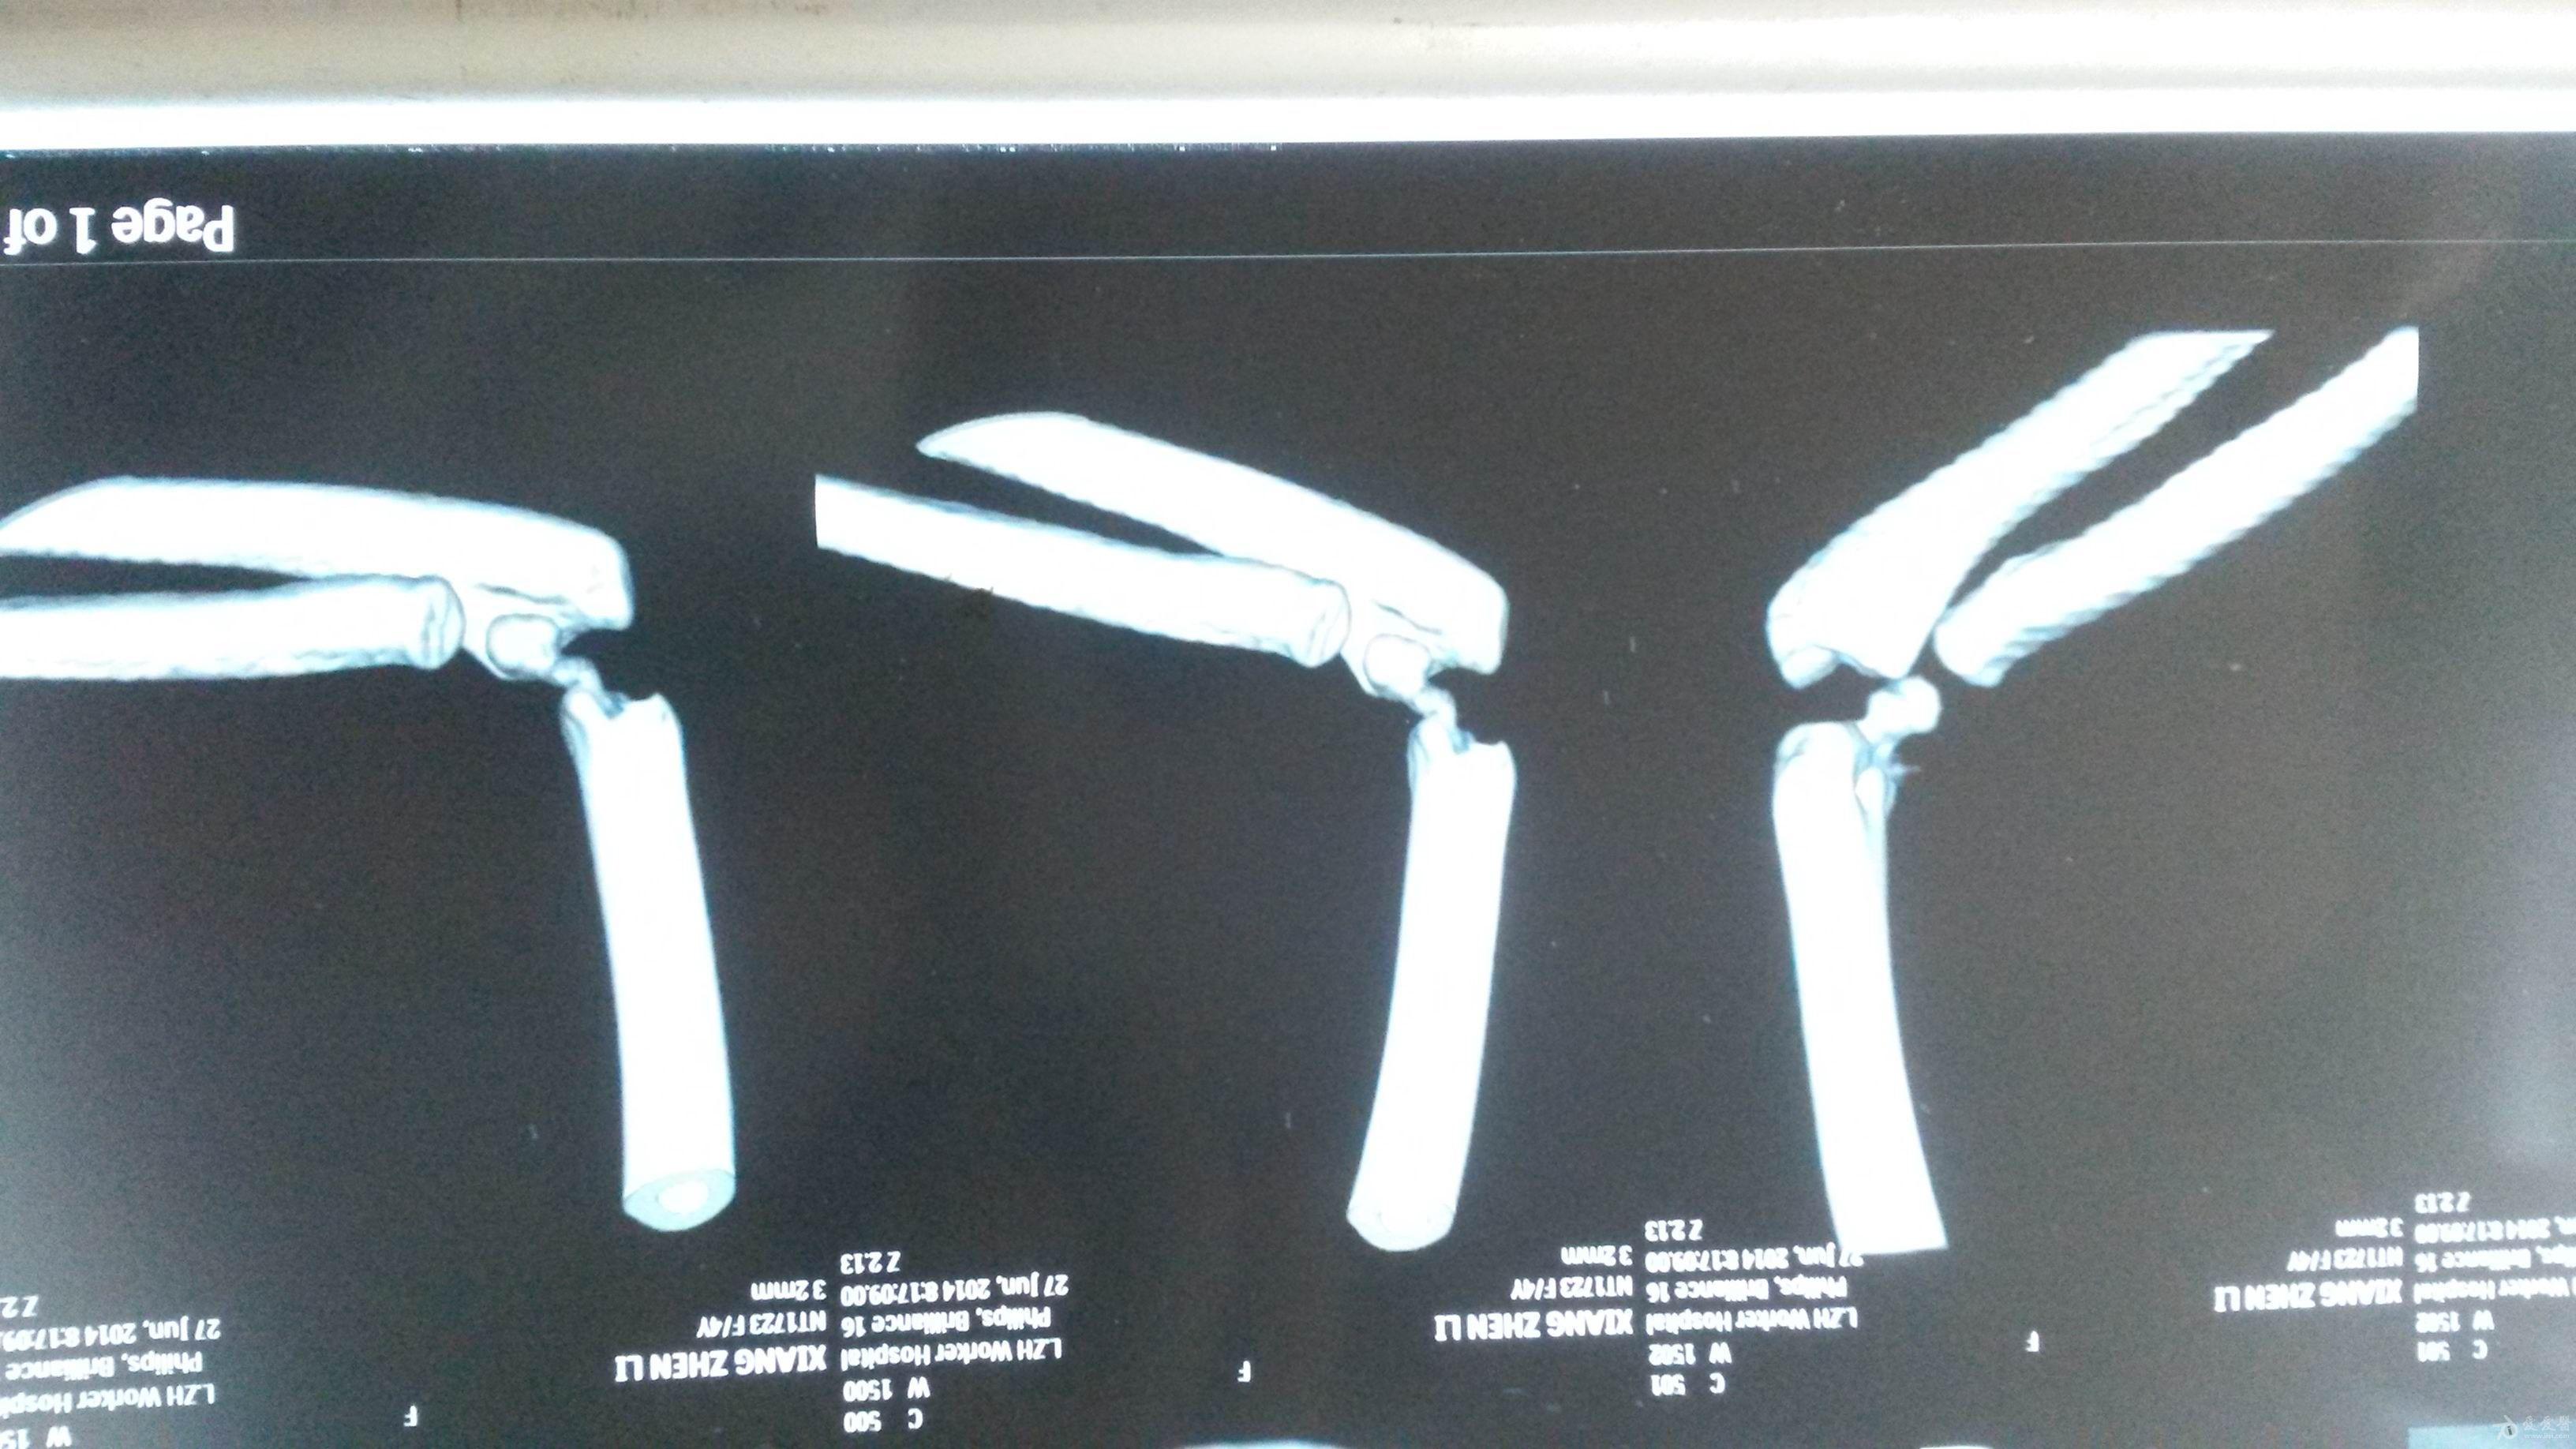

肱骨外髁骨折程度[s0]肱骨外髁骨折分型[s1]肱骨外髁骨折的临床表现[s2]肱骨外髁骨折Ⅲ型复位手法[s3]肱骨外髁骨折,保守治疗可以吗[s4]小儿肱骨外髁骨折[s5]儿童肱骨外髁骨折,医生不说你很可能永远都不会知道的[s6]不同类型的肱骨外髁骨折[s7]肱骨外髁骨折概述[s8]六、肱骨外髁骨折 - 图1[s9]六、肱骨外髁骨折 - 图2[s10]图片[s11]肱骨外髁骨折 m.haodf.com[s12]图片[s13]肱骨外髁骨折[s14]img[s15]肱骨外髁骨折.[s16]分期矫正儿童肱骨外髁骨折不愈合伴肘外翻畸形[s17]肱骨外髁骨折[s18]肱骨外髁骨折翻转90°,复位后克氏针或螺钉固定(自ao)[s19]右肱骨外髁骨折切开复位内固定术[s20]img[s21]img[s22]赵景新's media[s23]一例儿童右肱骨外髁骨折病例[s24]肱骨外髁骨折,保守治疗可以吗[s25]小儿肱骨外髁骨折[s26]肱骨外髁骨折固定[s27]肱骨外髁骨折 www.iiyi.com[s28]小儿肱骨外髁骨折的诊断和治疗[s29]右肱骨内外髁骨折[s30]图36-48 肱骨外髁骨折的不同程度移位 a型无移位;b型中度移位;c型完全移位伴旋转[s31]肱骨外髁骨折 www.haodf.com[s32]肱骨外髁骨折 www.haodf.com[s33]问:左肱骨外髁骨折,左肘关节脱位,6.[s34]儿童肱骨外髁骨折 - 小红书[s35]儿童肘关节损伤之--肱骨外髁骨折[s36]▲右侧肱骨外髁骨折闭合复位克氏针固定及石膏固定术后。“幸亏在掉落的[s37]肱骨外髁骨折 www.guahao.com[s38]肱骨头及外髁骨折,求诊治方案,手术还是非手术[s39]